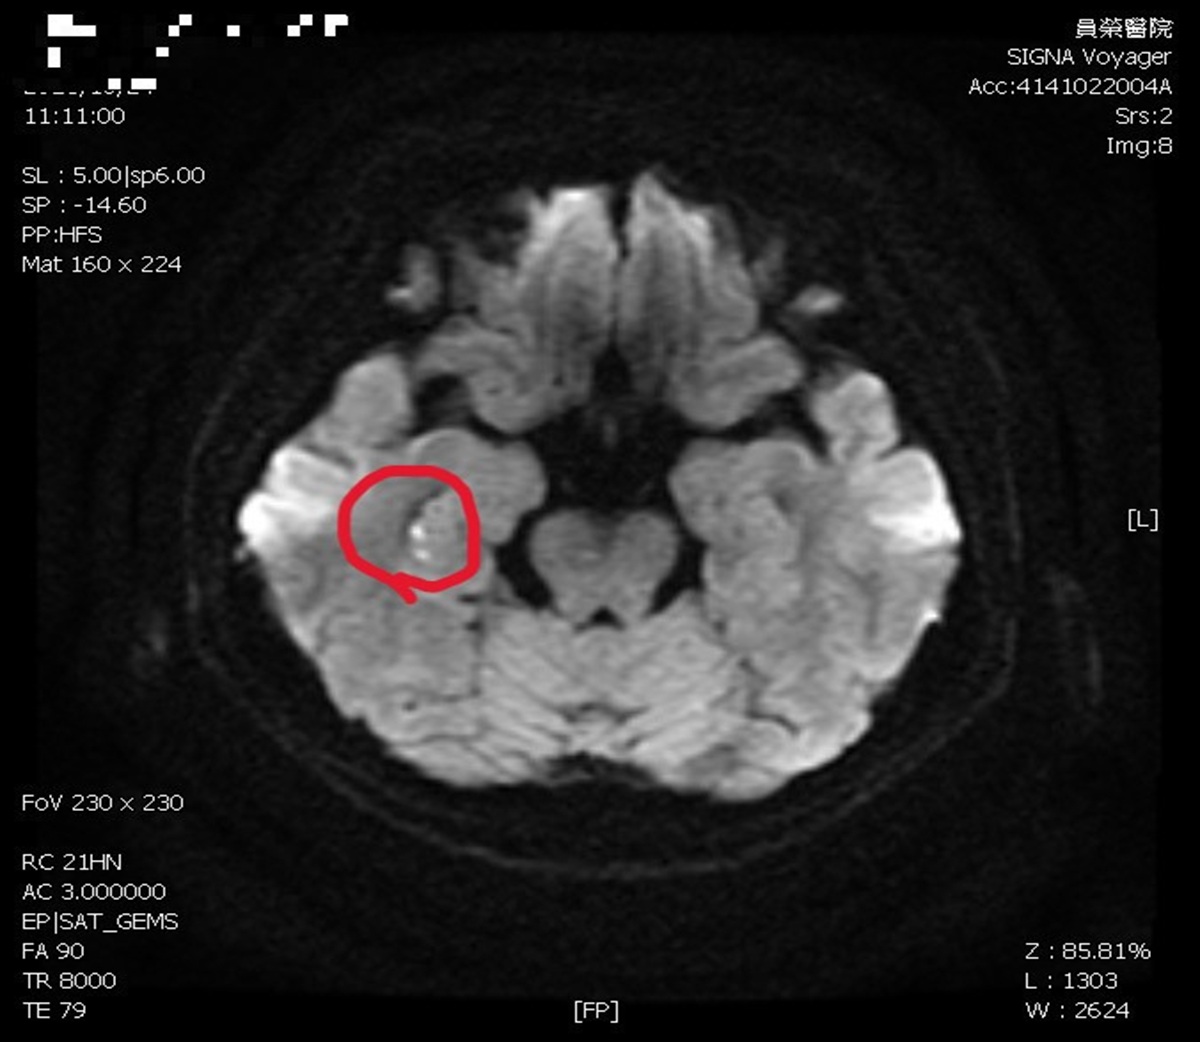

陳彥秀醫師表示,患者接受腦波檢查是正常;但核磁共振,看到她右側海馬迴出現一點亮亮的影像。海馬迴與記憶功能密切相關,證實她「短暫性全面失憶」狀況,是因為情緒過於激動,中風所造成。